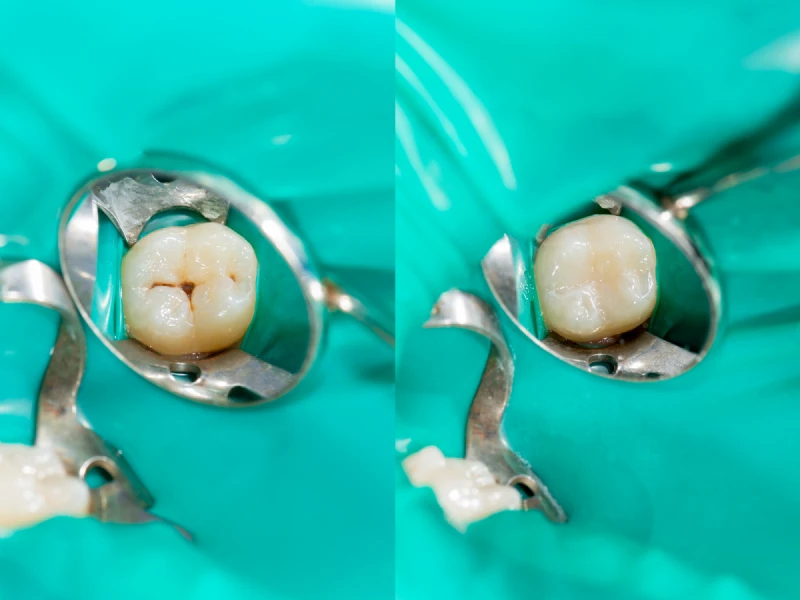

Composite fillings are very popular nowadays. They’re not too expensive, and they blend in perfectly with the rest of the teeth. It can be almost impossible to differentiate a person’s natural teeth from a composite filling they have put in. They’re also structurally sound. The main disadvantage of composite fillings is that they’re not very long-lasting and have a life of about five years.

Ceramic fillings are made of porcelain. These are very expensive, but rightly so. Just like composite fillings, ceramic fillings blend in with the rest of the teeth. The advantage they have over composite fillings is that they’re more resistant to staining. Ceramic fillings also last about 15 years or more so you don’t have to worry about changing them.